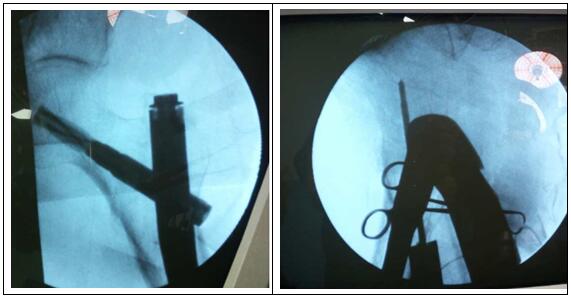

图片二:(术中照片)

科主任杨志奎带领曹熙、田涛、安蒙蒙、张凯迪医师,经充分讨论,考虑到患者高龄,合并高血压、冠心病等多种基础疾病。自身恢复能力不强,身体机能较差,已承担不起传统开放性手术所带来的创伤。为改善患者生活质量,再次站立起来,根据骨折类型,为老人选择行闭合复位股骨近端骨折PFNA髓内内固定方式。手术时长约35分钟,术中透视骨折复位满意,内固定装置位置适当。术后第1天,即指导患者行左髋、膝关节屈伸活动锻炼,术后第2天可坐起。